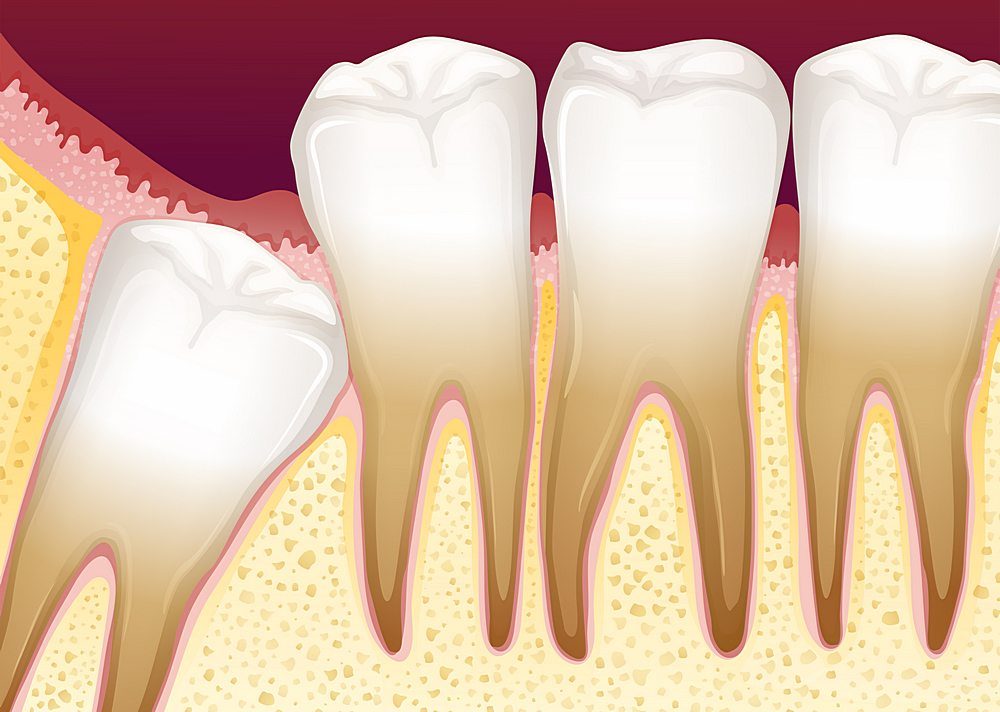

Дентальная галерея: ретинированный зуб клык и его лечение